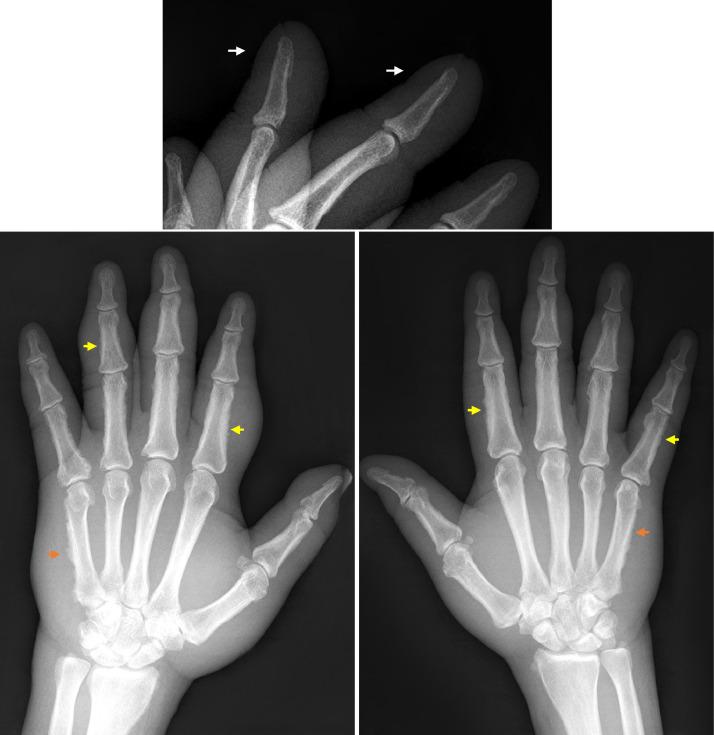

Thyroid acropachy is a rare complication of autoimmune thyroid disease with characteristic imaging findings. Clinically, it presents as nail clubbing, swelling of digits and toes, almost always in association with thyroid ophthalmopathy and dermopathy. On radiographs, it manifests as prominent irregular and spiculated periosteal new bone formation in the hands and feet. We present a 52-year-old man with history of Graves' disease who presented with swelling of the hands and feet. Radiographs of the hands and feet revealed marked diffuse soft tissue edema and characteristic periosteal new bone formation most consistent with thyroid acropachy.

甲状腺性杵状指(趾)是自身免疫性甲状腺疾病的一种罕见并发症,具有特征性影像学表现。临床上,其表现为杵状指(趾)、手指和足趾肿胀,几乎总是与甲状腺眼病和皮病相关。在X线片上,其表现为手足部位明显的不规则且呈毛刺状的骨膜新生骨形成。我们报告一名52岁患有格雷夫斯病的男性,他出现了手足肿胀。手足X线片显示明显的弥漫性软组织水肿以及与甲状腺性杵状指(趾)最为相符的特征性骨膜新生骨形成。